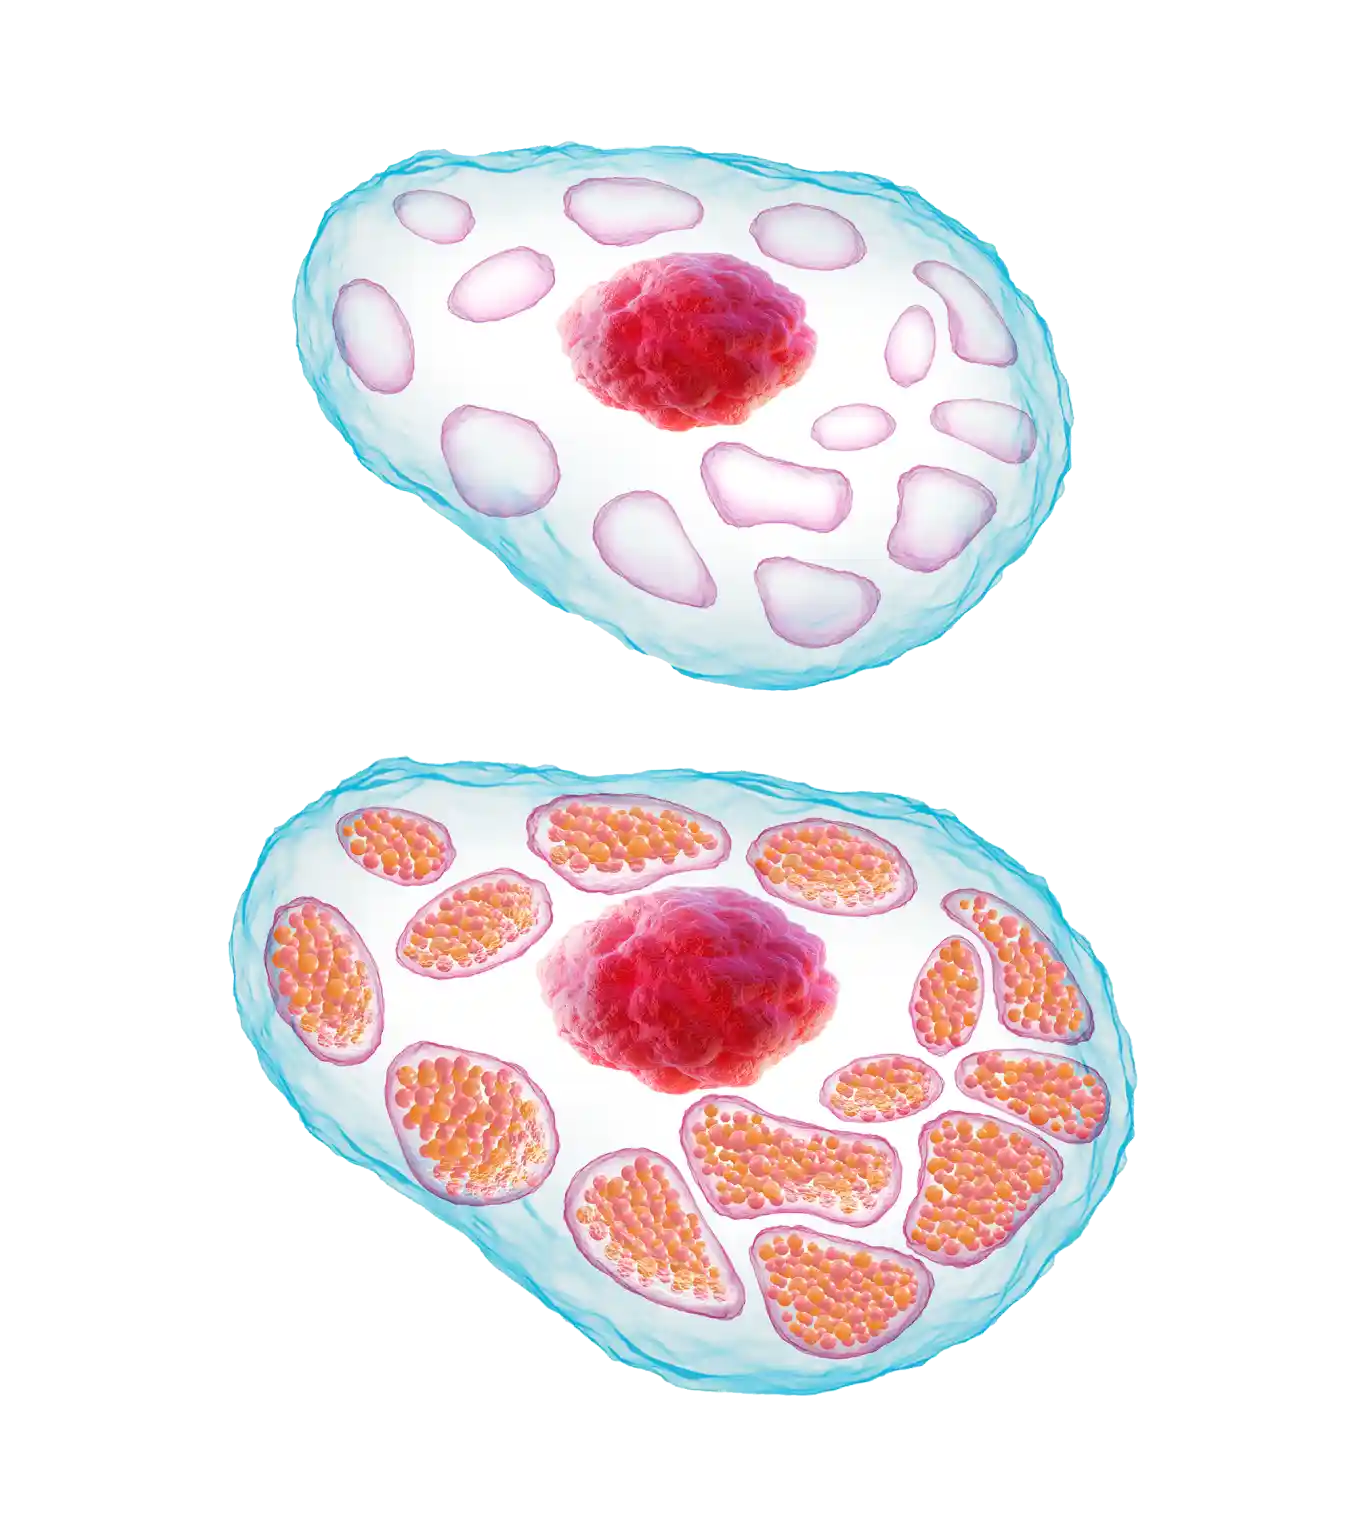

Healthy Cell

Gaucher Cell

Healthy Cell

Gaucher Cell

GD1 is a lysosomal storage disorder characterized by a deficiency of the enzyme glucocerebrosidase.2 This is caused by mutations of the gene that controls production of this enzyme.3

Without sufficient glucocerebrosidase, its substrate glucocerebroside accumulates within the lysosomes of macrophages, leading to the formation of ‘Gaucher cells’.1,4

‘Gaucher cells’ are engorged macrophages, visually characterized by a displaced nucleus and a lysosomal architecture that is distorted from its normally spherical shape.1,4,8

- Gaucher cells infiltrate organs and tissues enriched in cells of the mononuclear phagocyte system, e.g., the spleen, liver, and bone marrow.1,9,10

- Over time, they displace normal cells resulting in progressive impairment; the liver and spleen may become enlarged, which can interfere with normal functioning and cause a painful and swollen abdomen.1,8,9,11

- Displacement of hematopoiesis by Gaucher cell accumulation within the bone marrow can lead to anemia and thrombocytopenia, which in turn result in bleeding problems and can compromise the strength of the skeletal system.6,11

Healthy Cell

Gaucher Cell

Healthy Cell

Gaucher Cell